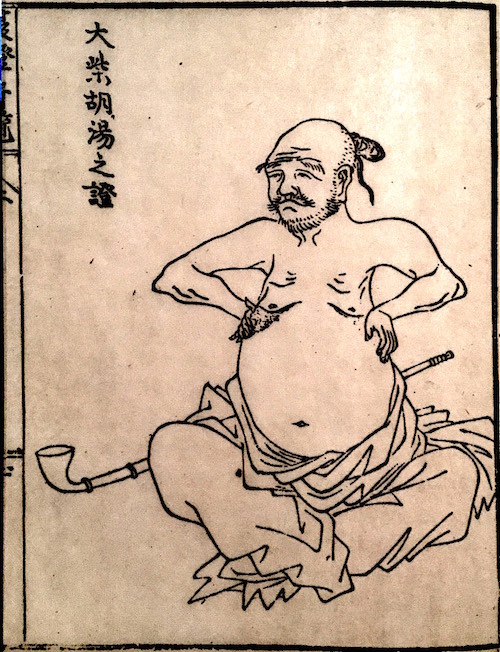

前回に続き腹證奇覧に記載されております、

小柴胡湯についてです。

小柴胡湯

胸脇苦満ノ毒、浅薄ナル者ノ圖也。

按之而知ノ傳、圖ノ如ク、

脇下肋骨ノ端ヲ指ニテカヽゲミルニ、コタユルモノアリ。

是薄キ苦満ノ毒ナリ。

又、心下ヲ按テ少シクコタユルモノナリ。

是即痞鞕ナリ。世二積聚ト号スルモノ、此ノ證多シ。

原文の緑の下線部①〜③について

腹部の邪の現れ方についてです。

①厚深ナルモノハ見易ク

(邪が深くにあるものは見やすい)

②浅薄ナルモノハ見難シ。

(邪が浅くにあるものは見難い)

③毒浅薄ナルカ、如クニシテ、大二深キモノアリ。

(邪が浅くにあるようにみえても実は深くにある場合がある)

③は邪が腹底にあり、

表には現れないものである。

と記載されています。